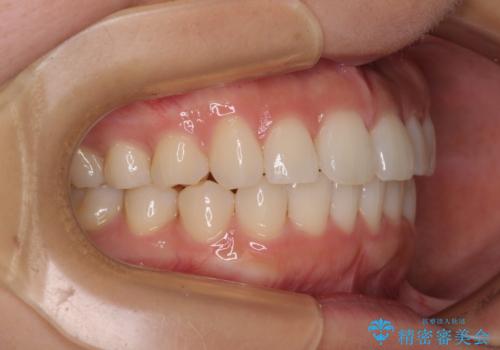

上下前歯のデコボコ ワイヤー装置で楽して改善

- メタルブラケット

- 1年6ヶ月

治療中は大きなトラブルもなく、予定の1年半でスムーズに治療を終えることができました。